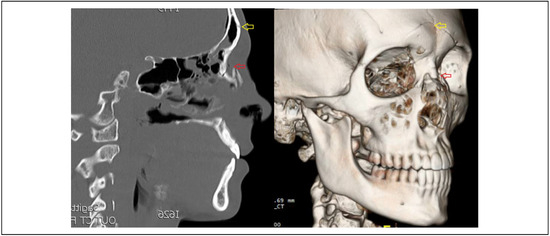

An Endonasal Incision Adds a Second Vector of Manipulation During Percutaneous Reduction of Fractures Involving the Frontonasal Region

Study Design: A case report. Objective: To describe a modification of percutaneous reduction of frontal sinus and/or naso-orbito-ethmoid (NOE) fractures, adding an endonasal intercartilaginous incision to provide a second vector of manipulation. Methods: Case report with particular attention paid to surgical technique, followed [...] Read more.

Study Design: A case report. Objective: To describe a modification of percutaneous reduction of frontal sinus and/or naso-orbito-ethmoid (NOE) fractures, adding an endonasal intercartilaginous incision to provide a second vector of manipulation. Methods: Case report with particular attention paid to surgical technique, followed by a brief review of relevant literature. Results: Technique: A Carroll-Girard screw is used to engage the thickest part of the anterior wall of the frontal bone through a stab incision just superior to the frontonasal junction. An endonasal intercartilaginous incision is then made and a Cottle elevator is introduced to manipulate the fracture from the inferior aspect of the frontonasal junction. The percutaneous screw and the endonasal elevator provide perpendicular vectors for manipulation, thereby improving ability to reduce fractures when percutaneous traction alone is not successful. The technique is described here in a patient with anterior table frontal sinus fractures combined with posteriorly displaced Markowitz type 1 NOE fractures. Conclusion: While percutaneous reduction of frontal sinus fractures has been previously described, this report adds a subtle but important modification both in indication and technique for optimizing reduction while maintaining surgical simplicity and minimizing morbidity. Full article